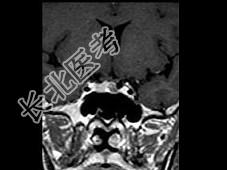

- 单项选择题女,25岁, 双侧泌乳,月经不调半年, 服药效果不佳,根据所提供图像, 最可能的诊断是 ( )

E、垂体微腺瘤